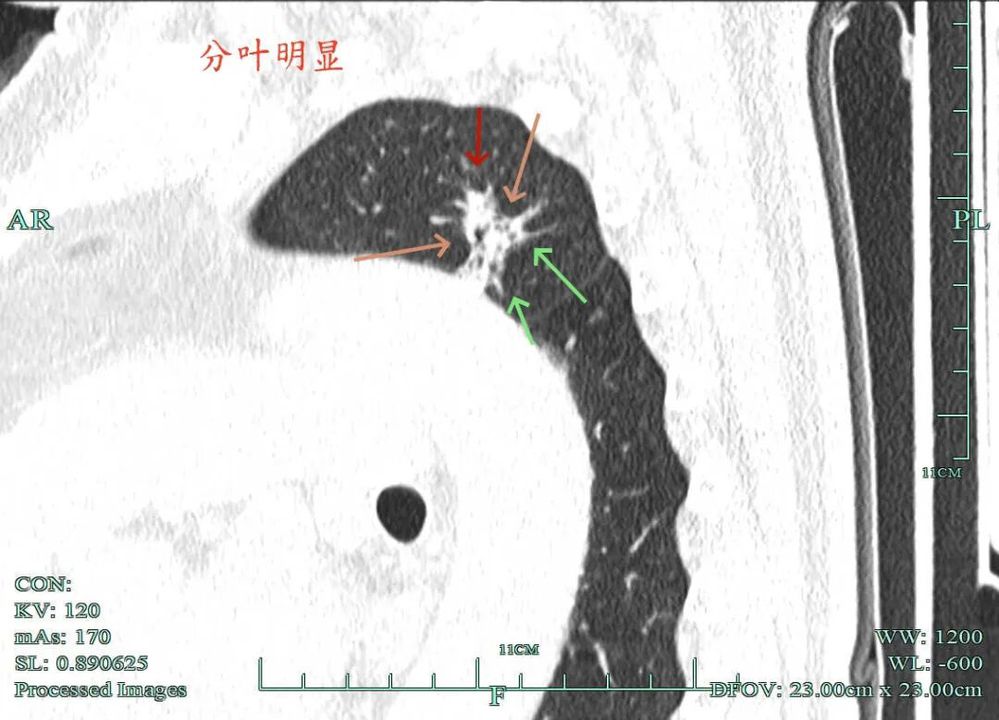

病灶到了2025年10月范围略有扩大,但不太厉害,不过密度明显增加,表面不平,整体轮廓与瘤肺边界清楚,灶内有条状密度增高,靠右侧向叶间裂处延伸,已经搭上胸膜了。这基本上就是浸润性癌的了!

杭州市肿瘤医院影像展示与分析:

左侧主病灶长达三年半时间的随访,当时就是混合密度,整体轮廓较清,随访不好转的话就是要高度警惕恶性的。现在病灶已经明显进展,实性成分增多明显,考虑浸润性腺癌可能性大。肺的粘膜相关B细胞淋巴瘤一般缺乏毛刺征,整体病灶的轮廓与边界会再偏模糊点。但从三年多随访范围增大不多,仍有磨玻璃成分来讲,个人认为已经有转移了的概率可能并高。大概率是中分化浸润性癌可能性大些。右侧病灶也是要考虑浸润性腺癌的,但一是它小些,二是处理要先处理风险更大的一侧,所以右侧病灶拟后续随访叶视其进展再微创干预。

今天这位结友的病理类型稍差于术前的预测,但从其三年多随访情况来看,进展不算大厉害,第10组与第12组淋巴结均阴性的话,还是真早期的可能性还是较大的。后续倾向暂随访观察,可以采取相对稍积极的随访策略,比如两年内4个月复查一次,三到五年内半年复查一次,五年后再年度复查;而且右侧的病灶要在随访进展或身体恢复良好后微创局部楔形切除。期间万一有转移,其实是伪早期的话,则基因检测并全身性治疗。其实今天这种病灶在临床中被判断为炎性的并不少见,尤其是非胸外科医生。因为胸外科的一般相对积极,警惕性高些。在我的公众号上其实也分享过多例这种看着似乎是炎性,但长时间随访不好转,或缓慢进展的病灶其实是浸润性腺癌的一种特殊表现,不少见的。我感觉此类病灶比较主要的临床特征是:1、密度多是混合磨玻璃密度,实性成分较明显,磨玻璃成分较淡,病灶显得密度较为杂乱不均;2、整体形态膨胀性不明显,收缩力不太强;3、灶内支气管通气及显得较为僵硬,血管征不典型,但表面多是不平不规则,较为毛糙,分叶多可见;4、随访或抗炎治疗不好转,进展不快,相对较为缓慢。容易被人以为是慢性炎症。但此时我们要注意几点:1、寻找磨玻璃成分,并观察瘤肺边界,尤其是磨玻璃成分与周围正常肺组织之间的界限是否清楚,清楚的多是恶性;2、靶重建从不同角度观察病灶形态,看病灶与邻近结构的关系,有无推压、破坏或支气管截断等征象;3观察病灶内部通气支气管的形态,扭曲、僵硬不舒展的多容易是恶性病变。总体上,要对“影像看着像慢性炎,但随访持续存在且有磨玻璃成分的”病灶要特别提高警惕,对于靠近边缘部分的,手术创伤不大的,要考虑“开刀带来创伤与随访导致的风险”之间的利弊权衡。我的根本理念仍是:淡化最后病理结果,从风险角度考虑问题!